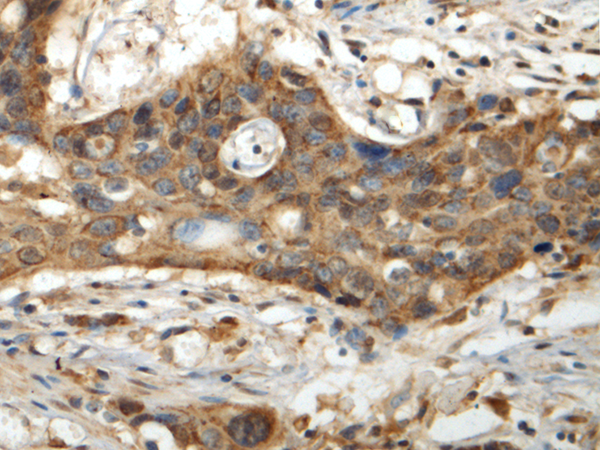

IHC positive control: |

Human esophagus cancer |

IHC Recommend dilution: |

150-300 |